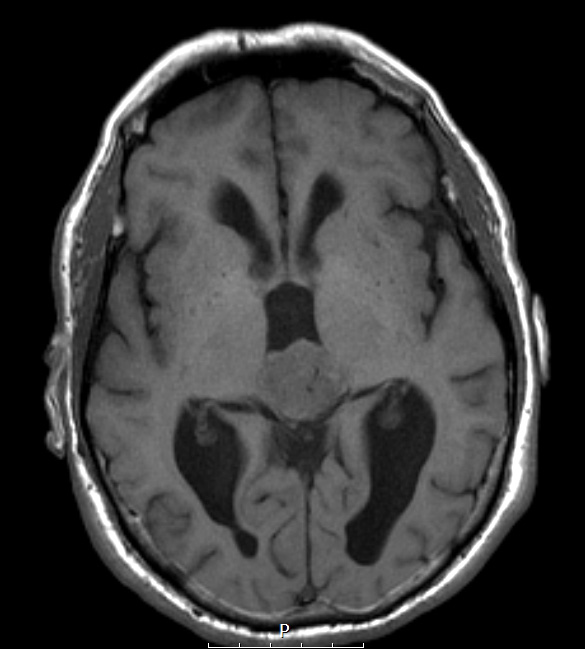

5A4,5 A T1-weighted scan is isointense with brain without contrast (5A4) and enhances strongly with contrast (5A5).